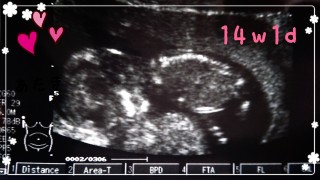

前回受診した時に比べて、大きくなっているし手足が長くなってるみたい。2wちょっと分くらい大きめの我が子。早く性別が知りたいなぁ。。

2回目の妊婦健診!1ヶ月、間が空き不安もありましたが、元気に動き回る姿が見れて涙が出そうになりました。エコーではベストショットが!こちらに向かって「ハーイ☆」と陽気に手を挙げてくれました(≧∇≦)他の写真も腕立てしてるっぽいものなどもあり、なかなか元気な赤ちゃん!経過も順調とのことなので、また1ヶ月後が楽しみです